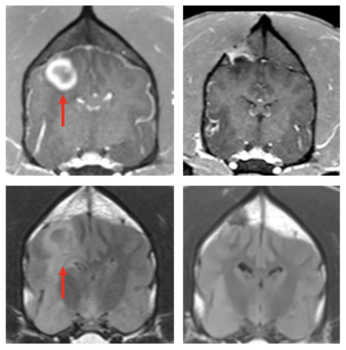

a grid of four black and white brain scans

Dog with glioblastoma showing the large bulky tumor (top left panel) and diffuse infiltration (bottom left panel) treated with the STING agonists 12 weeks later showing the disappearance of the bulky tumor (top right panel) and associated infiltration (bottom right panel).American Association for Cancer Research

The investigators tested a STING (STimulator of INterferon Genes) drug injected directly into the glioblastoma of five dogs that had previously been diagnosed with the cancer, which is the second-most common type of brain cancer in dogs. STING agonists can induce immunological responses that allow the immune system to fight otherwise immunologically resistant cancer cells.

MRI scans taken of the patients over the course of the 10-month trial revealed that some of the dogs, even with a single dose, responded to the treatment with apparent reductions in their tumor volume, including one complete response in which the tumor appeared to completely disappear, leading the team to conclude that this therapy can trigger a robust, innate anti-tumor immune response and may be highly effective on recalcitrant tumors such as glioblastoma.